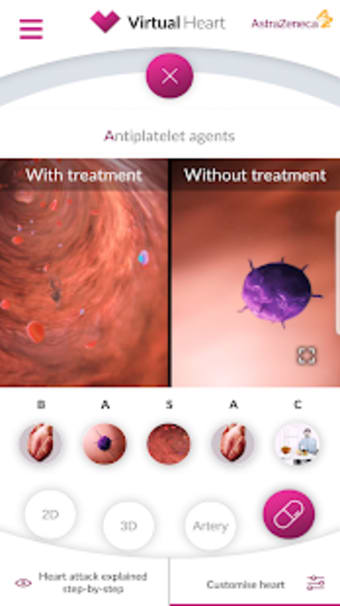

Virtual Heart - ANZ är en gratis programvara för Android, som ingår i kategorin 'Medical'.Om Virtual Heart - ANZ för Android